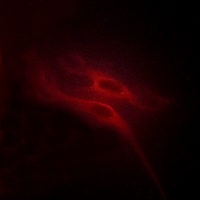

Immunofluorescent analysis of 5-HT4 staining in HeLa cells. Formalin-fixed cells were permeabilized with 0.1% Triton X-100 in TBS for 5-10 minutes and blocked with 3% BSA-PBS for 30 minutes at room temperature. Cells were probed with the primary antibody in 3% BSA-PBS and incubated overnight at 4 °C in a hidified chamber. Cells were washed with PBST and incubated with a AF594-conjugated secondary antibody (red) in PBS at room temperature in the dark.